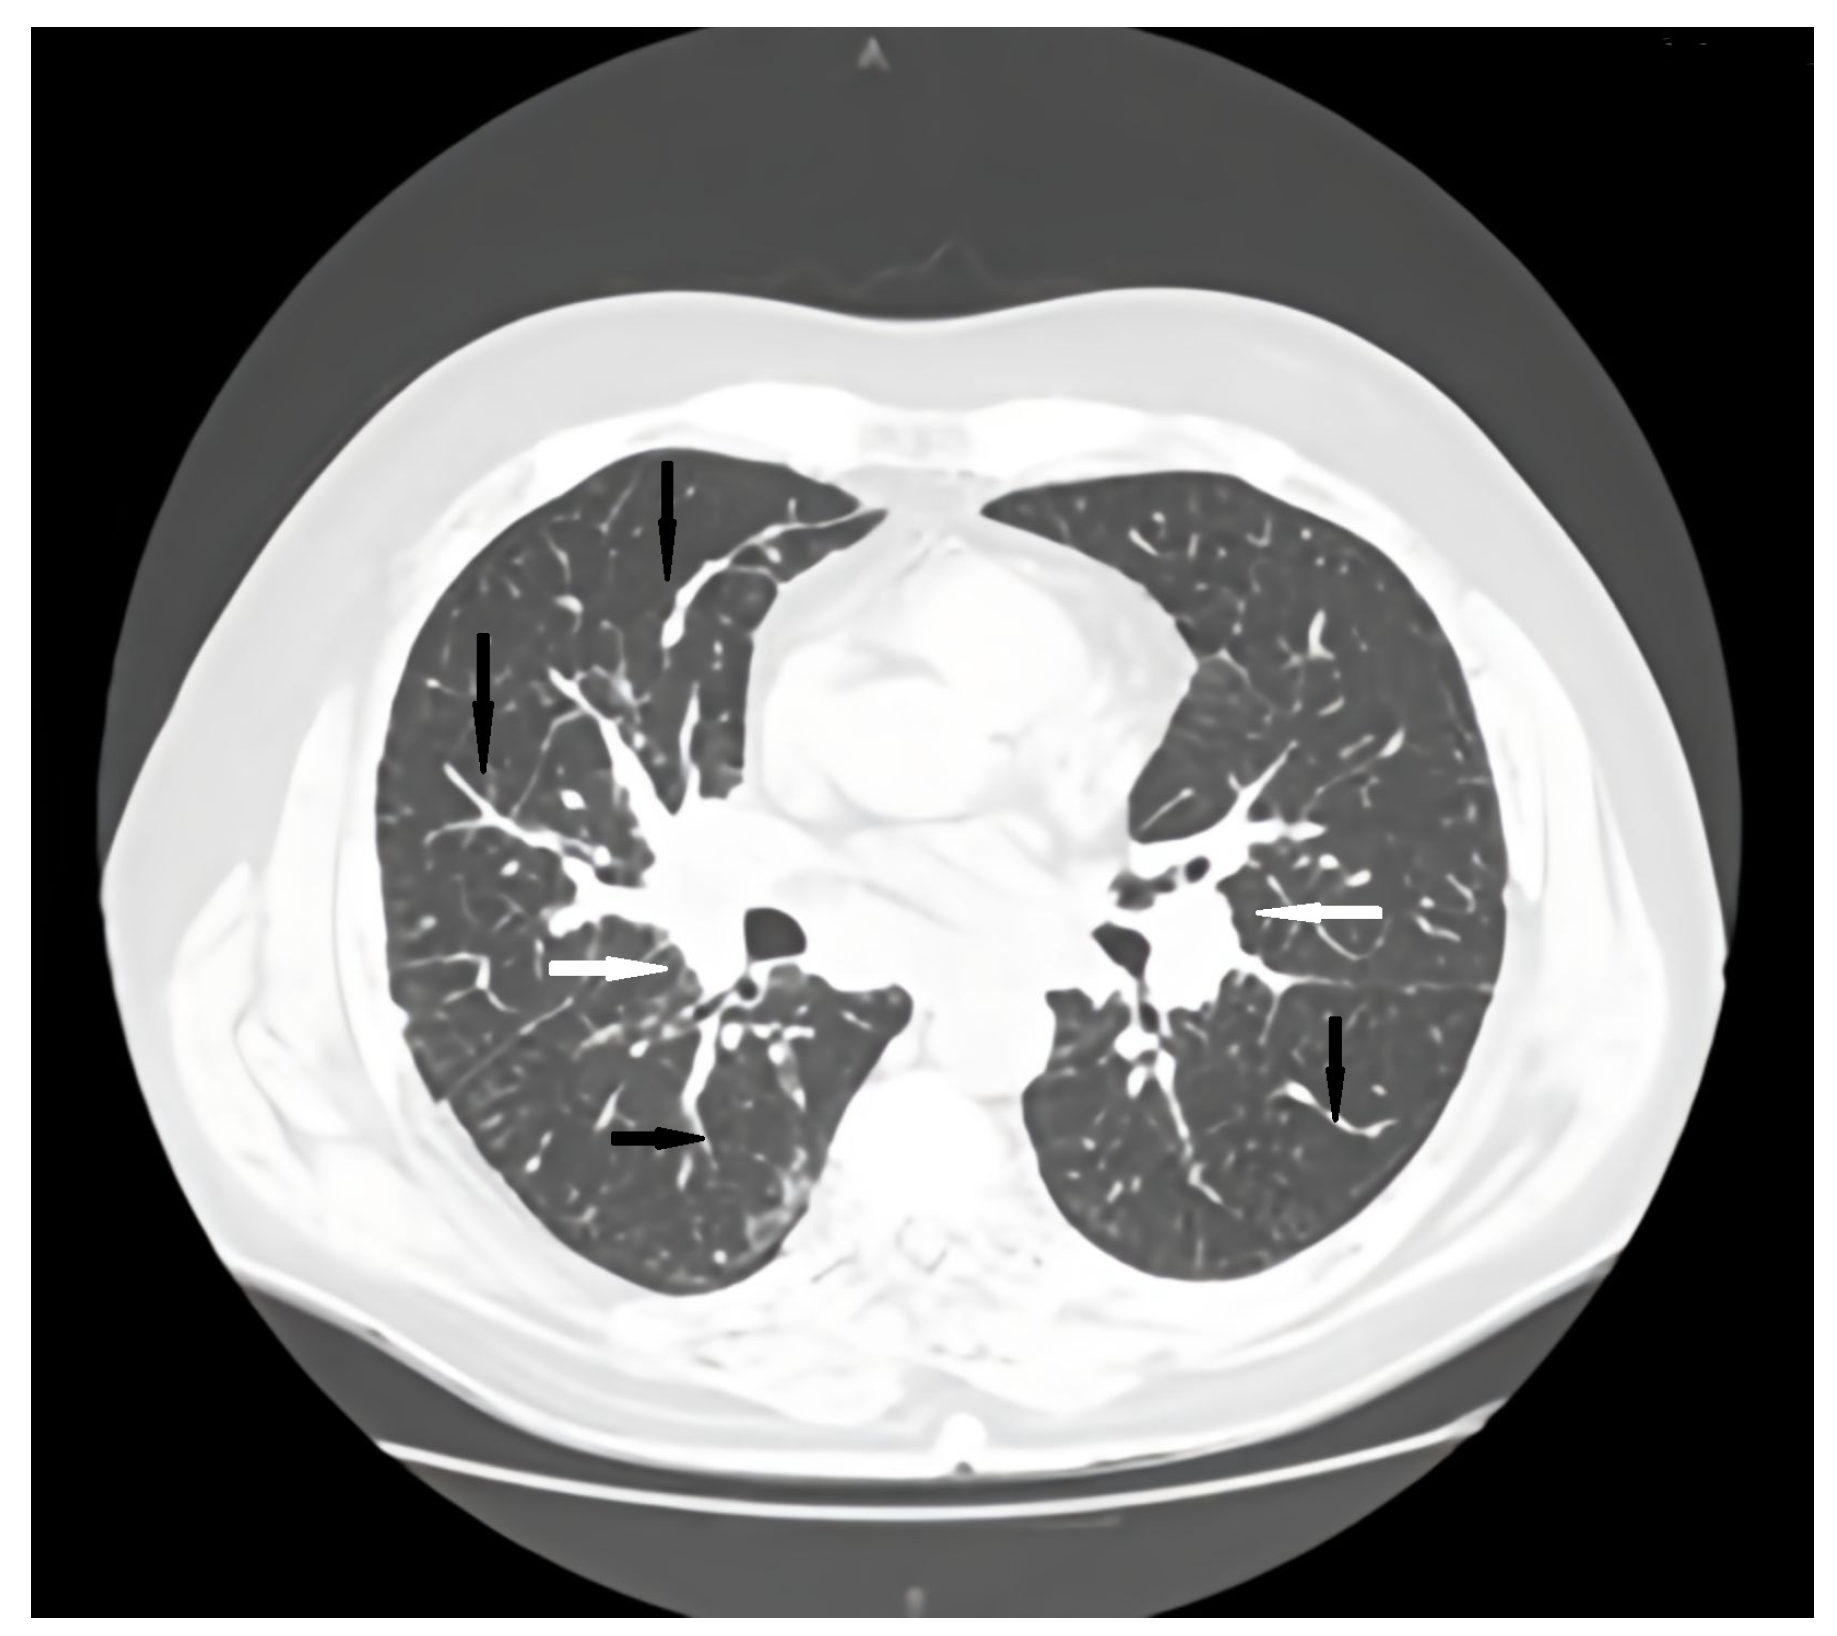

Regular pulmonology follow-up and periodic lung computed tomography (CT) scans showed a stable pattern over the years following the CVID diagnosis, characterized by a bilateral centrilobular micronodular pattern, irregular peribronchovascular thickening, bronchiectasis with mucoid impactations in the lower lobes, alveolar infiltrates, and mediastino-hilar adenopathies. After the onset of respiratory symptoms, a follow-up lung CT revealed similar interstitial findings suggestive of interstitial lung disease along with stable mediastinal-hilar adenopathies (Figure 1 and Figure 2).

Figure 1. Axial CT scan pulmonary window initial evaluation. A, anterior; P, posterior; black arrows, irregular peribronchovascular thickening; white arrows, adenopathy.